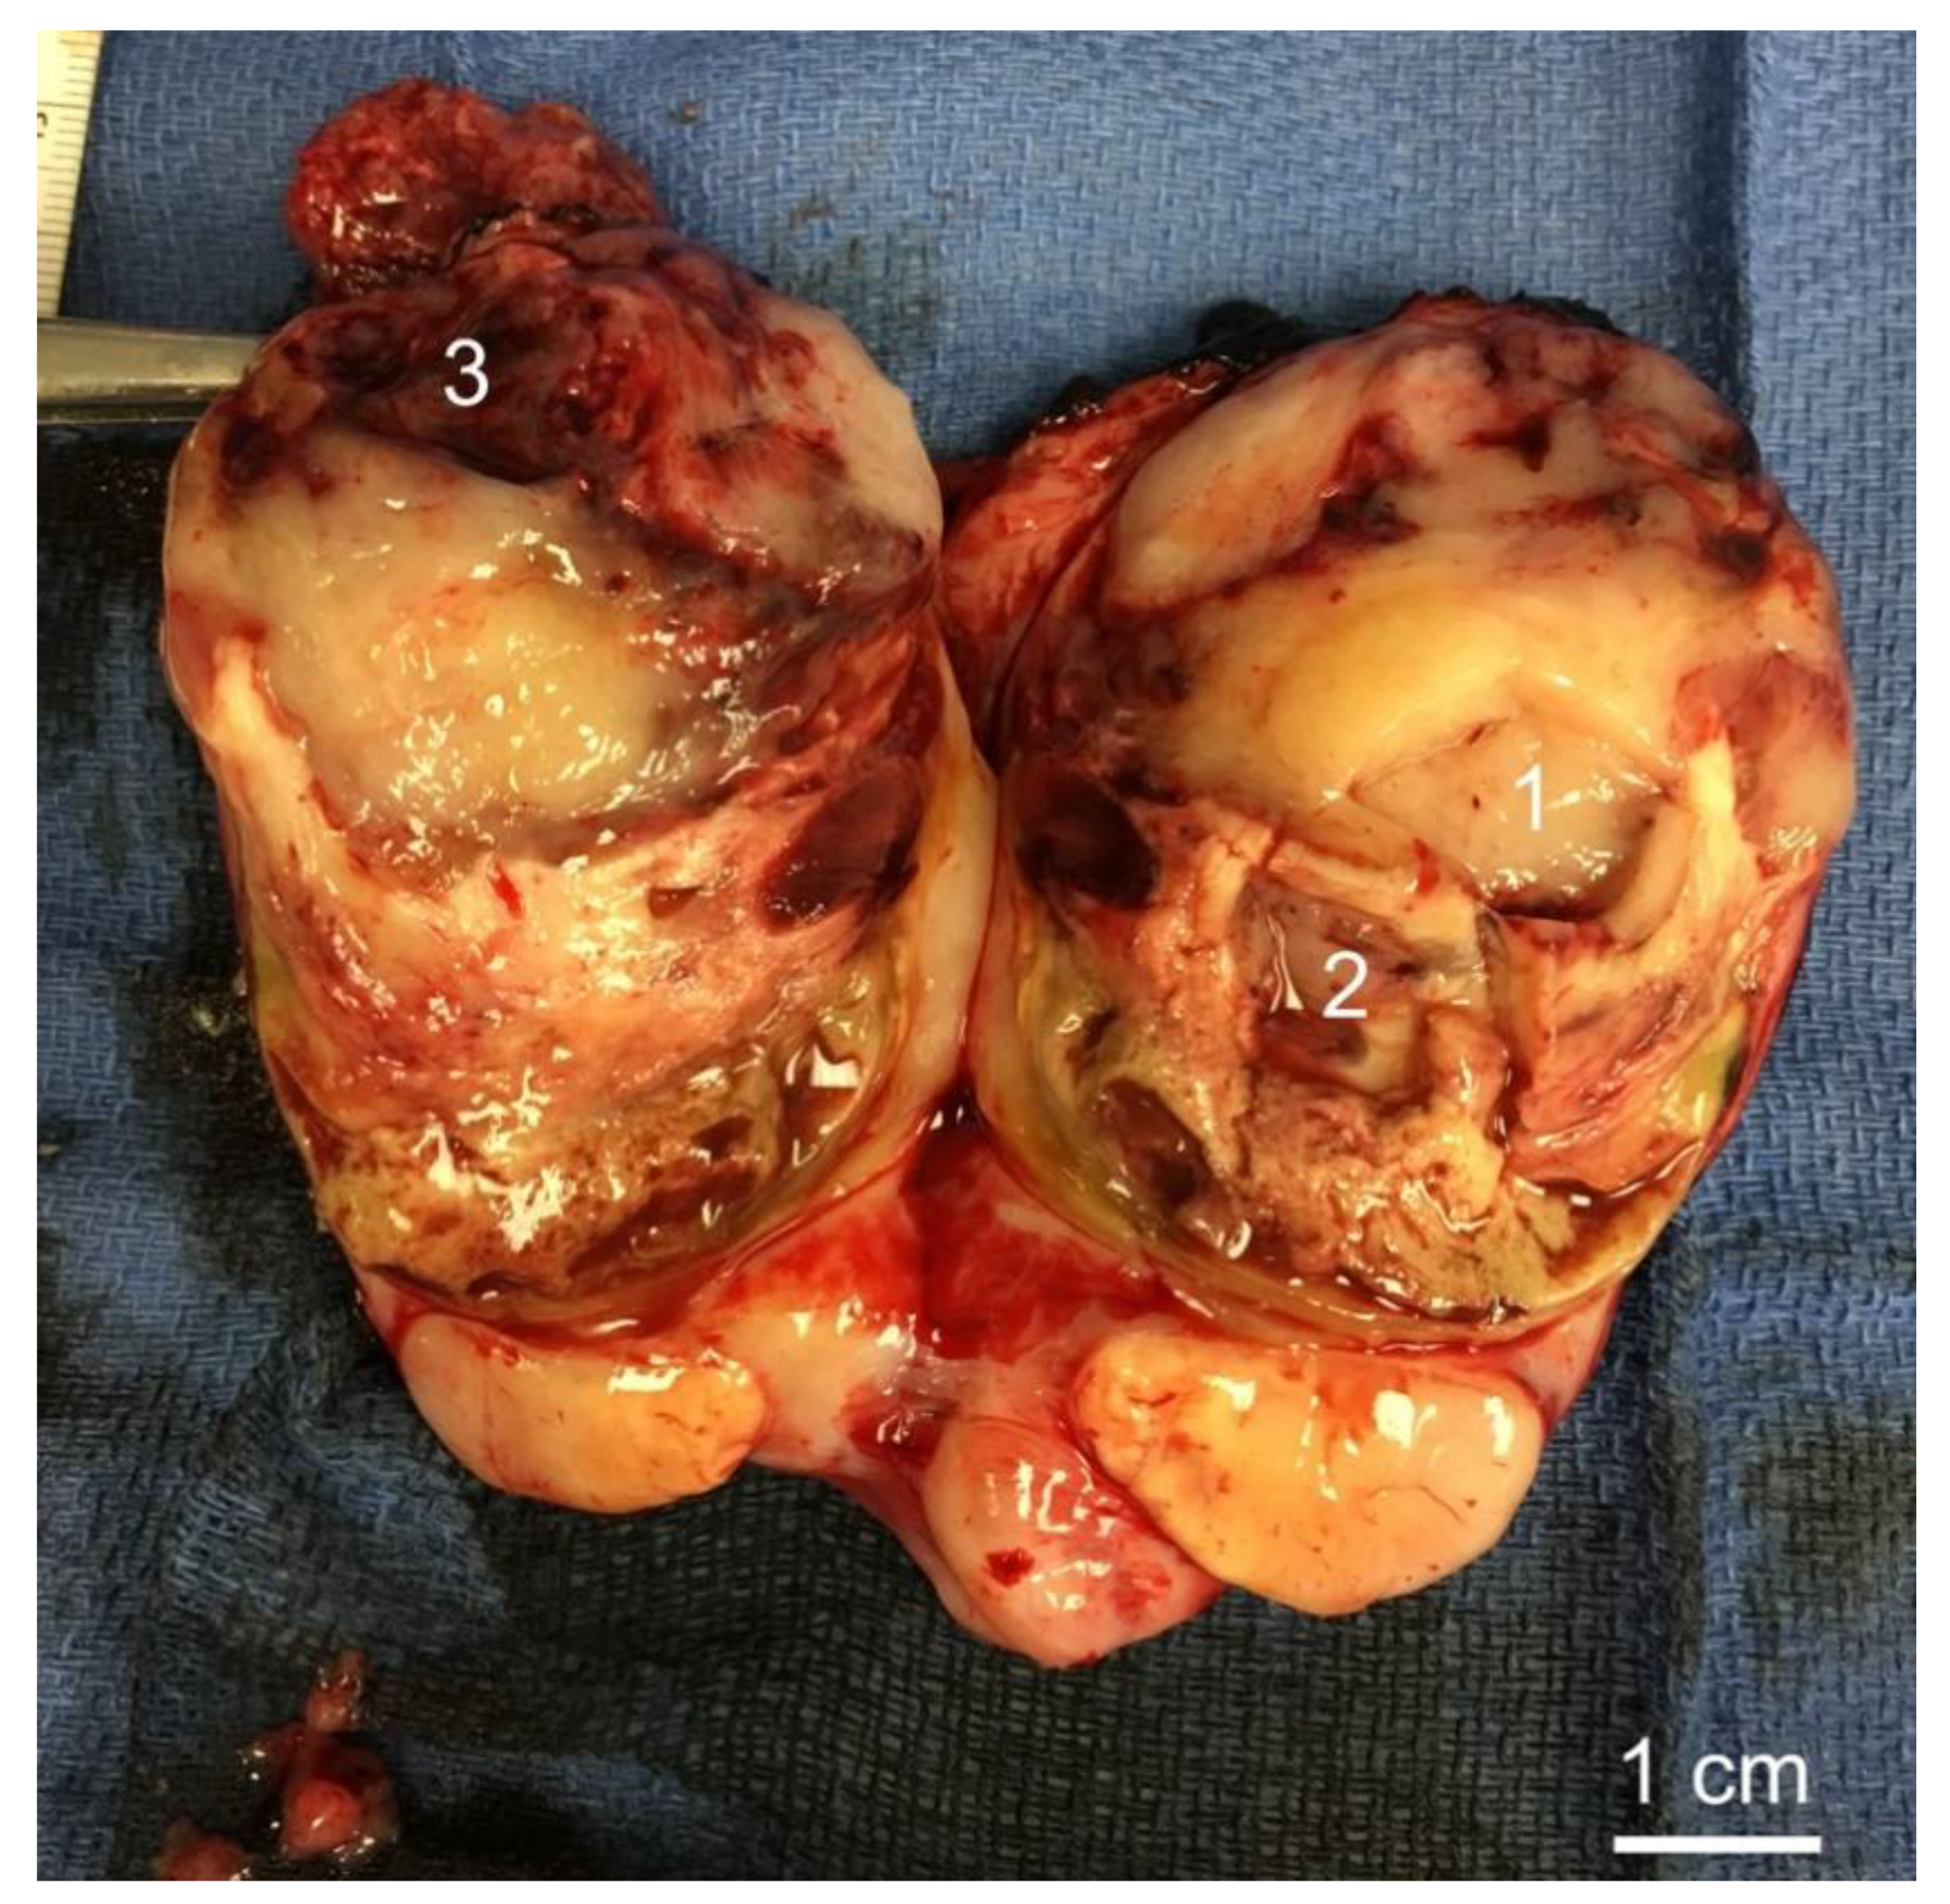

3.2. Histology of Biopsy Sites

| 40 | Male | Left neck | 10.2 cm, Grade 3 1 | Negative | Recurred | Lung | None | 33 |